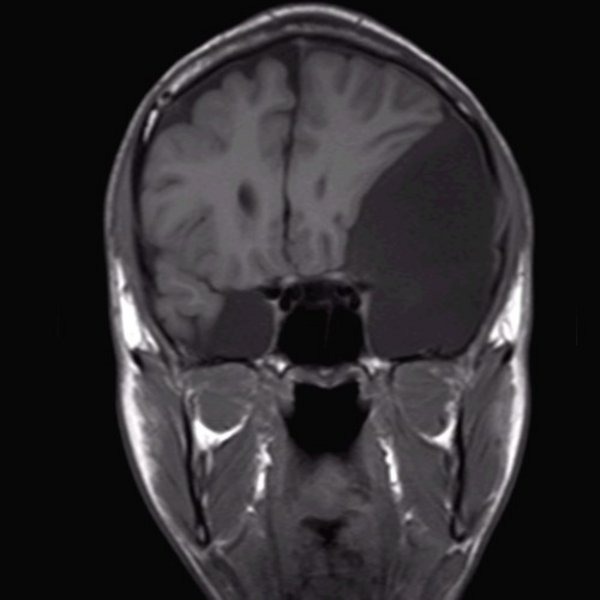

Arachnoidalzyste

Arachnoidalzyste T1 coronar